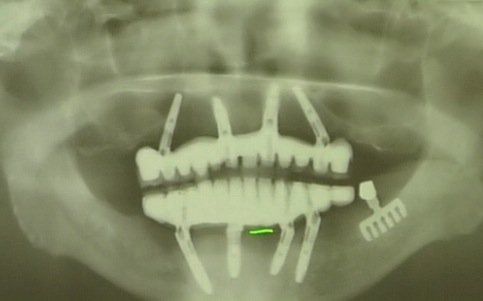

ブレードタイプのインプラント(右下。おざわ歯科医院・小澤俊文院長提供)

高齢者には他にもインプラント・リスクが存在する。1980年代、日本に第一次インプラントブームが起きた。当時、よく使用されていたものにカミソリのような形をしたブレードタイプがある。

このタイプは骨と結合せず、長期間経つと歯肉や骨に炎症を起こすケースが多いことが分かっているが、現在でも一部の歯科医が使用している。

ある高齢者の場合、ブレードタイプのインプラントが顔の皮膚を突き破って出てきた。“手術当時の医学的知見では、妥当な歯科治療だった”と歯科医やメーカーは主張するかもしれないが、個人で背負うにはあまりに大きな代償だ。